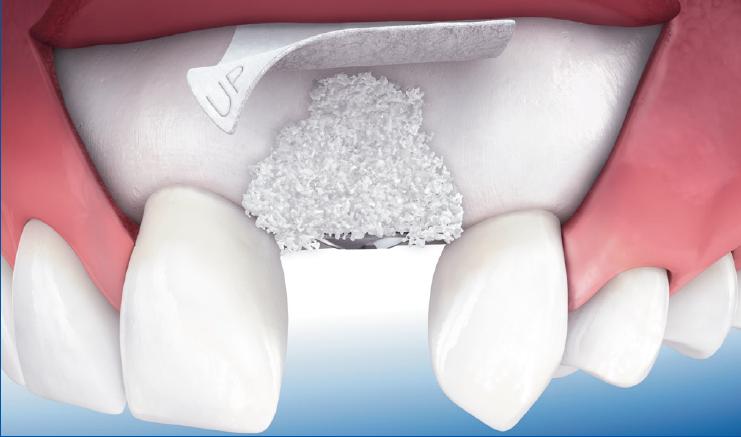

Augmentacija grebena je operativni zahvat kojim se nadomještava nedostatak kosti potreban za ugradnju implanta. U zavisnosti od područja i veličine defekta, koristi se nekoliko tehnika. Uzroci gubitka kosti mogu biti FIZIOLOŠKI, nakon vađenja zuba i usled starenja, i PATOLOŠKI, u koje spadaju parodontalne bolesti, kao i procesi u samoj kosti (granulom, cista, tumor). Gubitak kosti je prisutan i nakon oralnohirurških zahvata, traume, kao i dugotrajnog nošenja mobilnih proteza.

Nepravilnosti alveolarnog grebena u gornjoj i donjoj vilici mogu rezultirati nedostatkom koštane mase koja je potrebna za ugradnju implantata. Takve nepravilnosti mogu biti uzrokovane parodontozom, nošenjem proteza, razvojnim anomalijama ili povrijedama. Ne samo što takve nepravilnosti mogu uzrokovati probleme pri postavljanju implantata, već će stvoriti estetske probleme i onemogućiti optimalnu oralnu higijenu. Kako bi se ispravili takvi nedostaci kosti, greben se može augmentirati (povećati) koštanim nadoknadama.